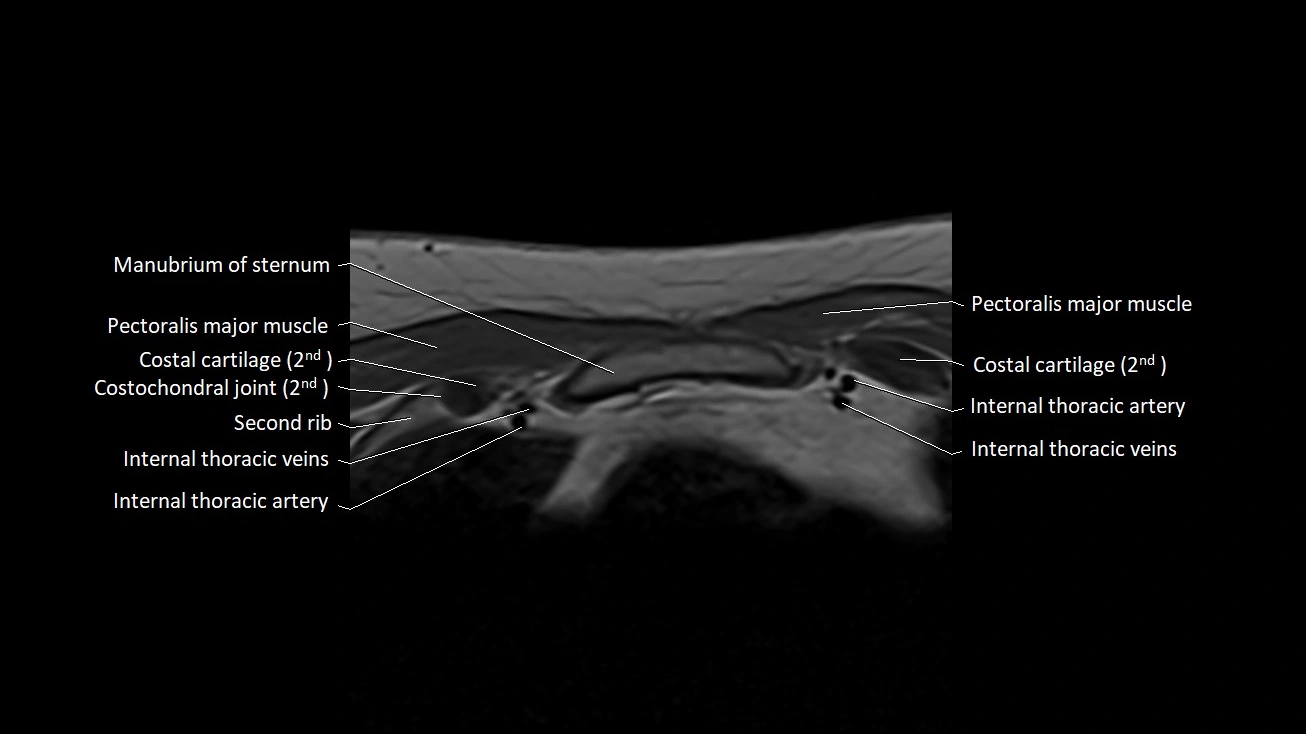

MRI images

image